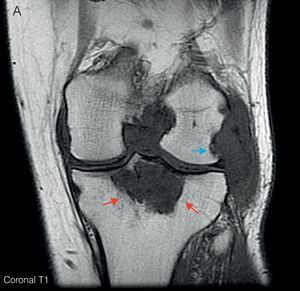

Ante las lesiones radiológicas de la rodilla izquierda, se completó el estudio con una RM de rodilla izquierda (fig. 3) en la que se objetivó proliferación sinovial difusa hipointensa en T1, con erosiones óseas en el margen posterolateral del cóndilo femoral. Un gran quiste de Baker con zonas de alta y baja señal en T2. y lesión lítica hipointensa en T1, con señal heterogénea en T2 a nivel de la epífisis proximal tibial con un diámetro máximo de 5cm, que tras administración de gadolinio mostraba realce, imagen característica de depósitos tofáceos.

A) RM de rodilla izquierda corte coronal en T1. Muestra proliferación sinovial difusa hipointensa, con erosiones óseas en el margen posterolateral del cóndilo femoral (flecha azul) y en escotadura intercondílea. Lesión lítica hipointensa en epífisis proximal tibial con un diámetro máximo de 5cm (flechas rojas). B) Corte sagital en T2. Se observa un aumento heterogéneo de señal a nivel de la lesión lítica en epífisis tibial (flechas rojas); junto con un gran quiste de Baker situado por detrás del vientre muscular del gemelo interno (flechas verdes), con zonas de alta y baja señal, correspondientes a hipertrofia sinovial. C) Corte sagital en T1 con Gd. Tras la administración de gadolinio se objetiva realce periférico a nivel de la lesión lítica tibial (flechas rojas) y del quiste de Baker (flechas verdes).